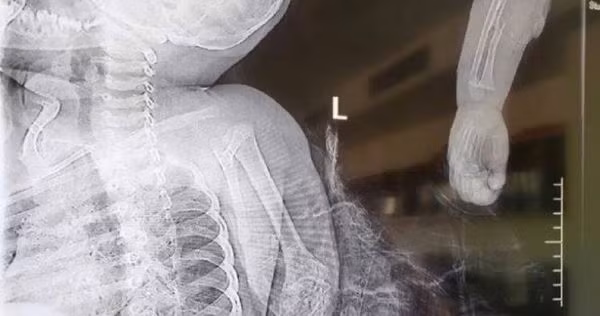

Trong ảnh là phim chụp X-quang cánh tay của bé trai bị chó ngao Tây Tạng cắn đứt lìa.